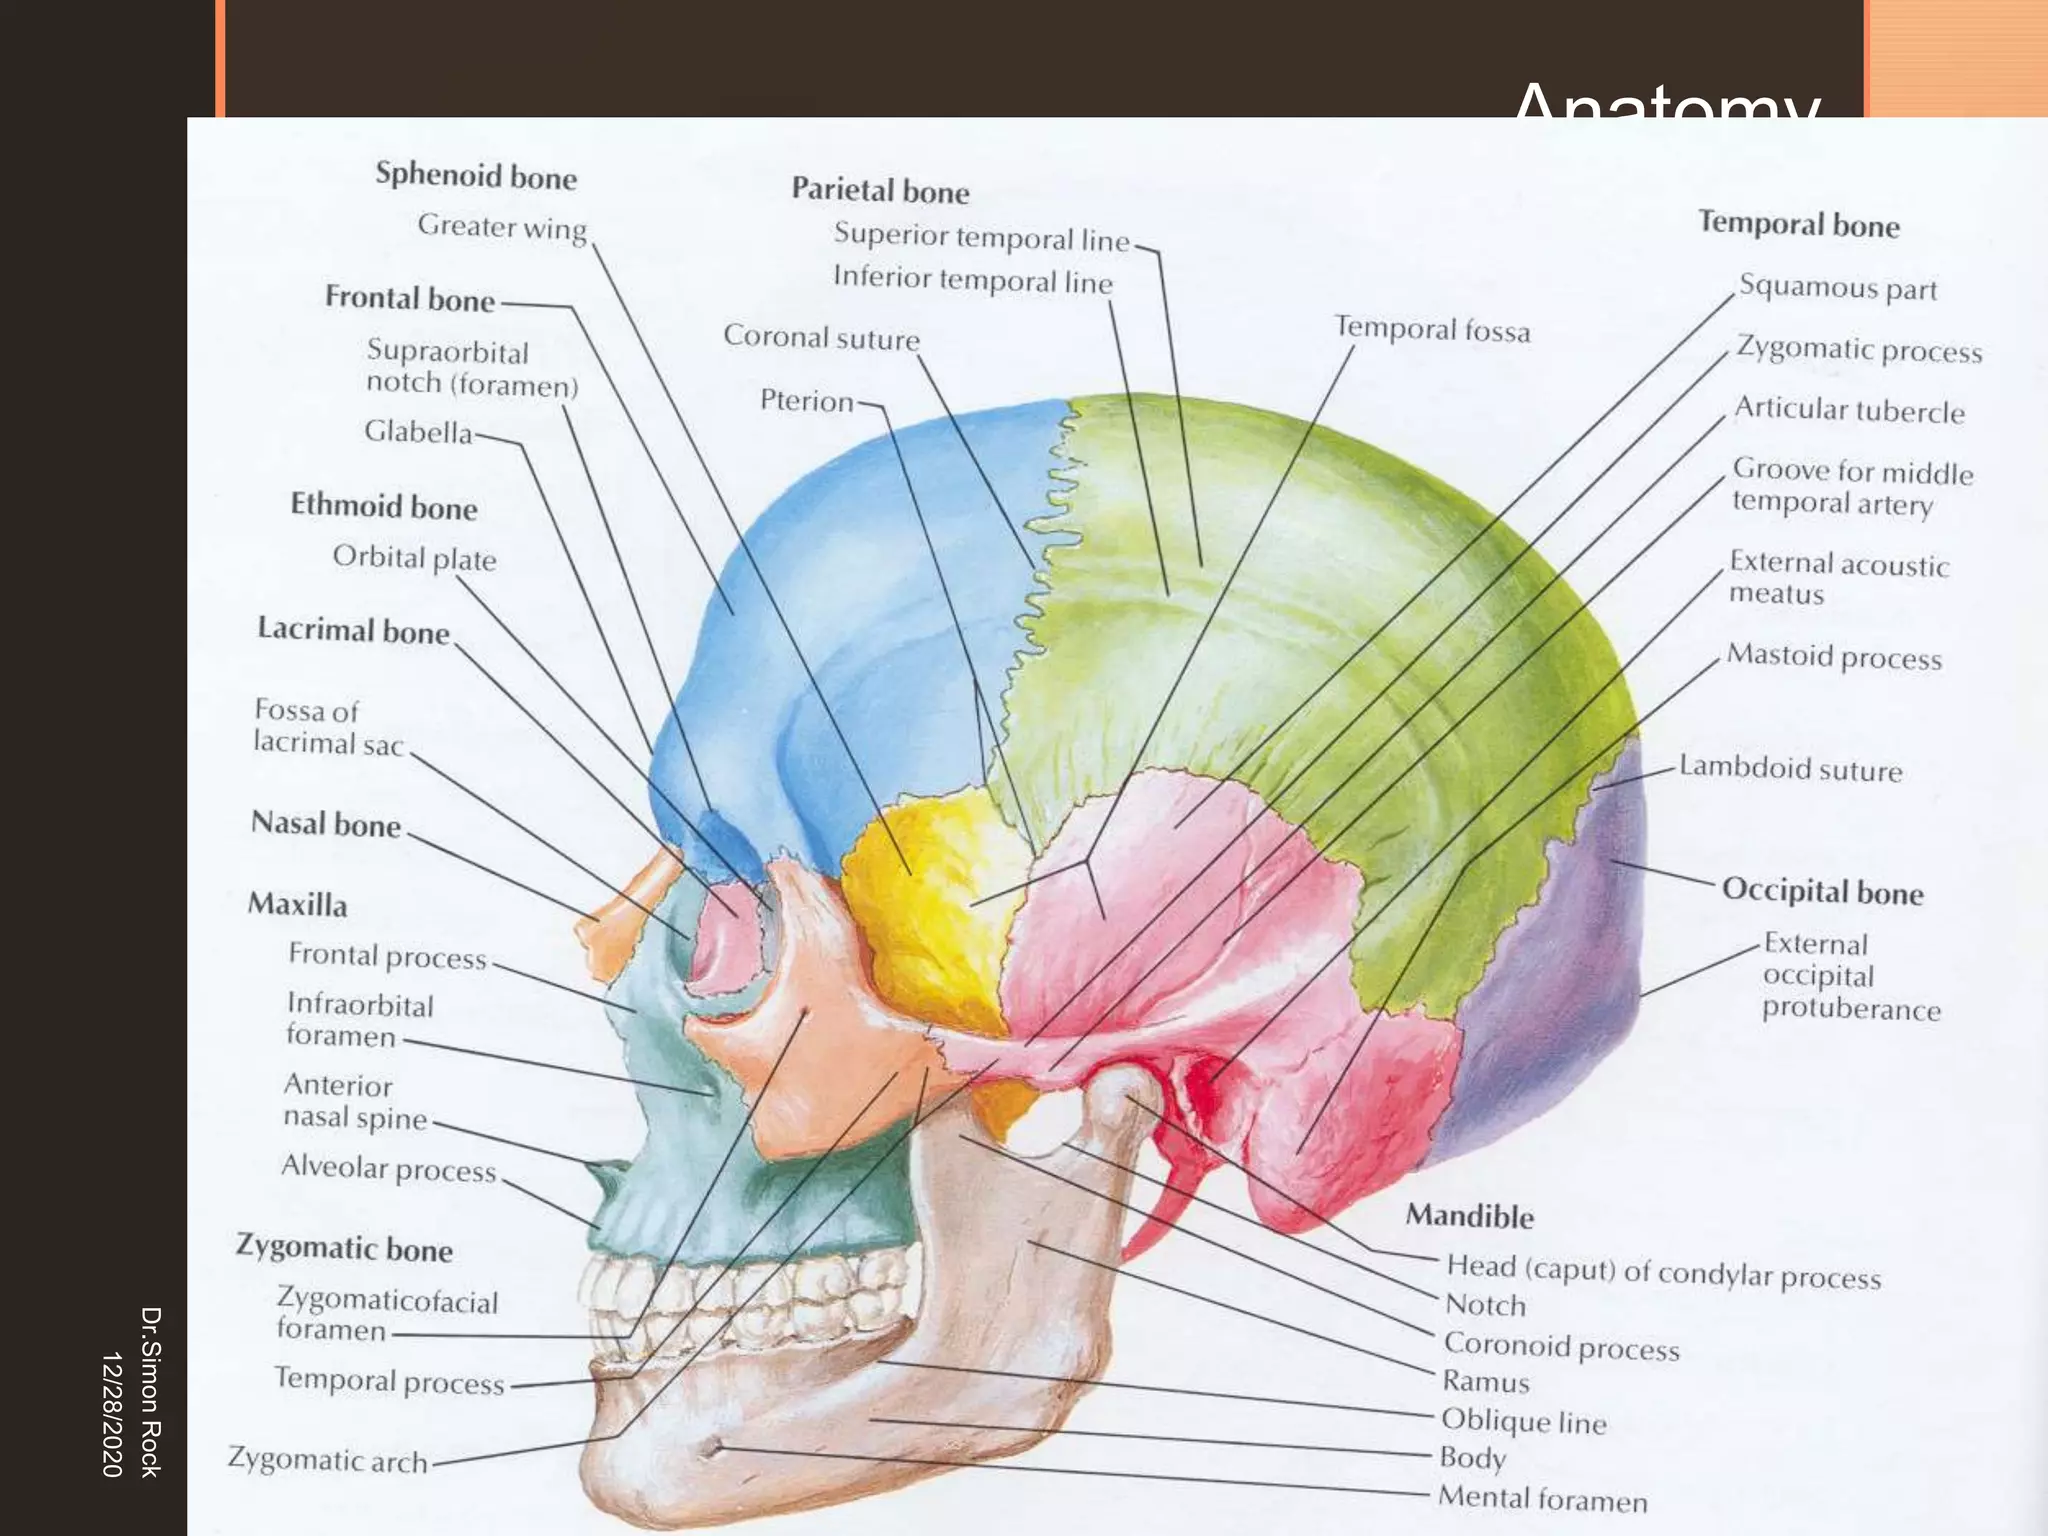

This document discusses the anatomy and fractures of the zygomatic bone. It notes that the zygoma forms the cheekbone and articulates with several other facial bones. Zygomatic fractures most commonly occur in the arch or body due to blunt trauma. Diagnosis involves checking for diplopia, ecchymosis, and other signs of orbital or facial bone involvement. Treatment may involve closed or open reduction based on the severity of displacement. Closed reduction techniques try to elevate the bone back into position without surgery, while open reduction requires surgical exposure and fixation of the fracture site.